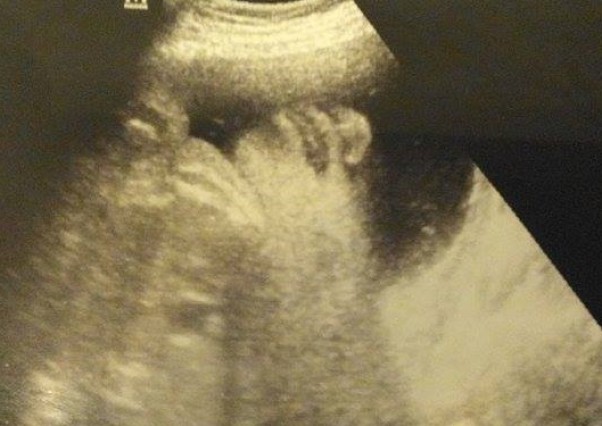

szok ! niedowierzanie ;) już tylko ktg co tydzień i mozemy się rodzić :) nasz Bąbelek w 34/35 tygodniu :) ciekawe po kim ma nosek ;d nasze 2129 gram szczęścia :* Kochamy moooocno :*